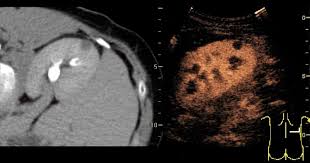

복부 초음파는 비침습적이며 방사선 노출이 없는 안전한 검사 방법으로, 초음파(ultrasound)를 통해 복부 내 장기들의 상태를 실시간으로 확인할 수 있는 진단 도구입니다. 복부 초음파로 알 수 있는 것 중에서는 특히 간, 담낭, 췌장, 비장, 신장, 방광, 대동맥, 소장, 대장 등의 상태를 파악할 수 있으며, 질환의 조기 발견에 탁월한 효과를 보입니다.

간 관련 질환

- 간암, 간종양: 실질 내부에 덩어리 유무 탐색